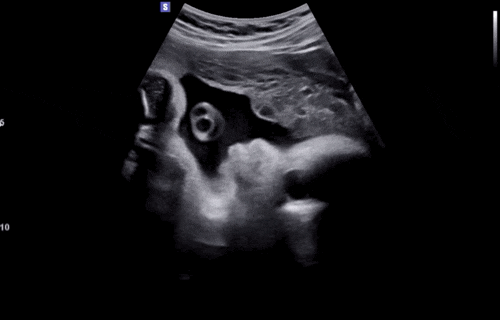

[임신 35주차 기록] 성심당&케익부띠끄 / 손수건&아기옷 세탁 완료 / 막달검사 / 심해지는 잇몸염증

설연휴 막바지 부지런히 놀러 다니고 막달검사와 치과 투어까지 한 ✨35주차 기록✨ <35주 0일차> 5...